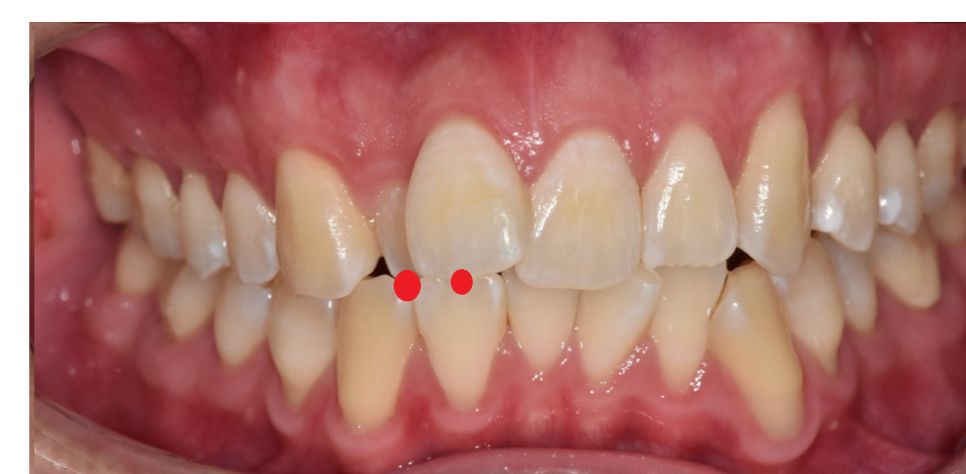

250714 또다른 부분적으로 반대교합 케이스

앞니는 부분적으로 반대교합이더라도

어금니 교합은 정상교합일 수 있는데요.

이런 경우 아래턱이 살짝 발달하여

반대교합으로 악화될 소지가 있는 케이스예요.

교합은 정상인데

배열은 부정교합이라니